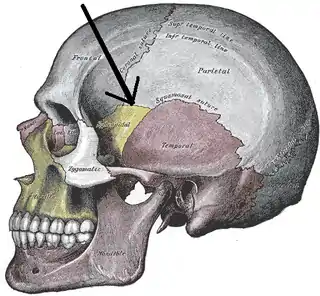

Vista lateral del cráneo. La flecha apunta a la sutura esfenoparietal sutura y el pterion está ligeramente a la derecha de la punta de la flecha. | ||